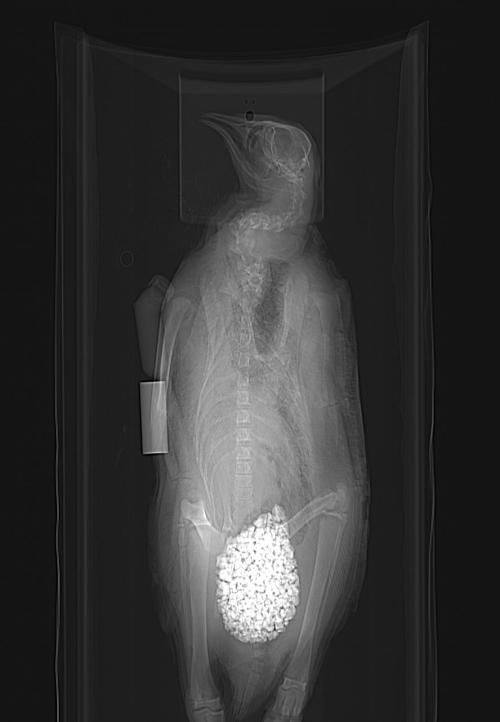

Calling all penguin experts! What’s up with this? Is that really how much gastrolith (stomach stone; near bottom of image) volume a penguin carries (answer after some literature reading: maybe yes!), or did a museum curator stick rocks up its bum? It seems very caudal in position, and this is consistent with other animals I’ve seen (some below). A paper on this phenomenon and potential role in ballast is here. Another here.